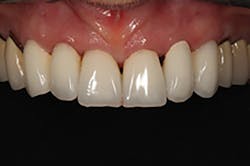

At the third clinical visit, the provisionals were removed, the preparations cleaned, and the final restorations cemented, without the need for contact or occlusal adjustments (figure 11). The patient was delighted with the outcome, which precisely duplicated the proposed treatment plan that was the basis for the provisional restorations she’d previously worn and the definitive restorations (figure 12).

Figure 11: Postoperative close-up retracted view of the cemented crowns

Figure 13: Postoperative facial view of the six CAD/CAM crown restorations

In the author’s experience, using Trios to create a “digital diagnostic wax-up” is far more effective for communicating a treatment plan than a traditional diagnostic wax-up. Patients are usually distracted by the color and confused with right and left, and they have trouble simultaneously viewing pretreatment and wax-up casts. In the case described here, explaining the treatment plan to the patient was enhanced by showing that her original tooth position appeared in gray, and the restorative plan appeared in white, which helped her immediately understand the plan. Additionally, reviewing the occlusal view dramatically demonstrated the planned correction to the original crowded position of her teeth (figures 13 and 14). However, one of the most noteworthy aspects of the digital diagnostic wax-up approach is the exact similarity between the diagnostic design, provisional restorations, and definitive restorations. Until now, no technology has ever enabled this level of precision and predictable duplication.